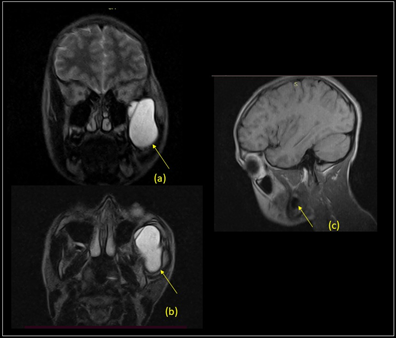

A 13-years-old male was referred to our medical department for an evaluation of progressive facial asymmetry. According to our clinical examination, the asymmetry was caused by a painless tumor on the lateral left face which was extended from the zygomatic region until buccal region and gradually increased in size since the patient was 6-years-old. The lesion was projected into the mouth; the skin and mucosa were normochromic, hard, well defined, adherent to the deep plane and moved on palpation (Figure 1). Open mouth limitation, difficulty during feeding, dysphagia, or odynophagia were not found. In the first instance, ultrasound (US) facial soft tissue was made with a 6.5 MHz convex transducer, reporting a big anechoic image with regular borders to 60 x 26 x 56 mm diameter with a 46cc approximate volume in the left zygomatic arch region. Following this, a non-contrast magnetic resonance image (MRI) was executed with open Philips Panorama machine performed at 3T, reporting a hyperintense image in T2-weighted (repetition time msec/echo time msec: 5,500/112) sagittal sequence and FLAIR-weighted (5,714/80) axial sequence; and isointense image in T1-weighted (24/80) coronal sequence to 54 x 30 x 51 mm diameter compatible with space occupant lesion with interior walls; lesion located between maxillary sinus and zygomatic arch bone left, from zygomatic region until buccal region; over to masseter and pterygoids muscles and below to temporal muscle with remodeling bone effects without infiltration (Figure 2); suggesting expansive cyst lesion and recommending histological examination.

Figure 2 (a-b) T2-weighted coronal and axial (repetition time msec/echo time msec: 5,500/112). (c) T1-weighted (24/80) sagittal sequence; showing images compatible with space occupant lesion with interior walls. Yellow arrows point to a lesion located between the maxillary sinus and zygomatic arch bone left, from the zygomatic region until the buccal region, over to masseter and pterygoids muscles and below to the temporal muscle.

MRI findings include a low-intensity cyst wall due to its fibrous nature, low to intermediate intensity on T1-weighted imaging, and high signal intensity on T2-weighted imaging. As a particular image, we describe an isointense image in T1-weighted (24/80) coronal sequence compatible with space occupant lesion within intracystic signal intensity interior walls, with remodeling bone effects without infiltration. These MRI characteristics could be related to the progressive growth of the clinic referred by our patient. In future studies it will be important to correlate.